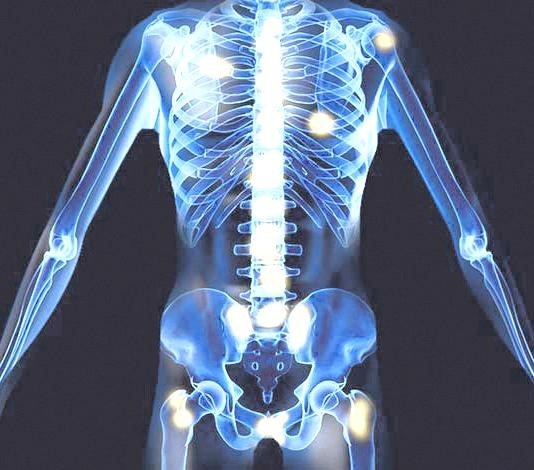

- 허리, 엉덩이, 다리 통증

- 설명: 전립선암은 뼈로 전이가 잘 되는 암입니다. 암세포가 척추, 골반, 허벅지 뼈 등으로 전이되었을 경우, 해당 부위에 지속적이고 심한 통증을 유발합니다. 이는 암이 상당히 진행된 경우에 나타나는 증상입니다.